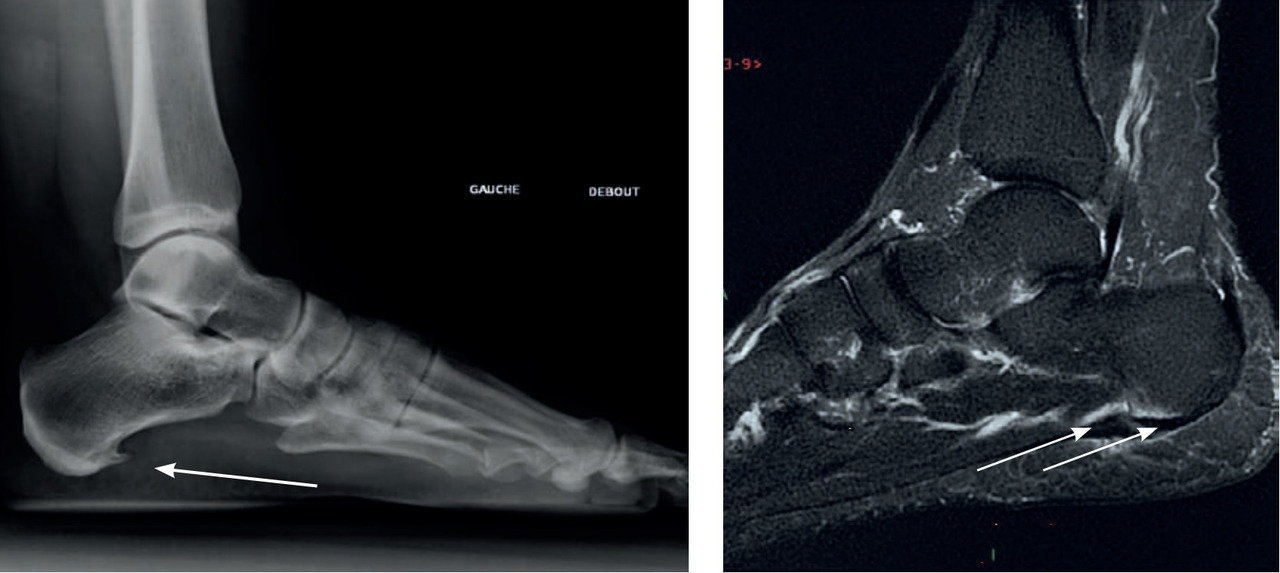

IRM : évalue l’os et les tissus mous, l’épaisseur de l’aponévrose et du tendon d’Achille, une inflammation localisée. Certains signes orientent vers une pathologie mécanique ou inflammatoire sous-jacente (fig. 3).

IRM : évalue l’os et les tissus mous, l’épaisseur de l’aponévrose et du tendon d’Achille, une inflammation localisée. Certains signes orientent vers une pathologie mécanique ou inflammatoire sous-jacente (

– à l’IRM : épaississement de l’aponévrose à son insertion, avec œdème osseux associé (hypoT1 et hyperT2 STIR) au niveau de l’enthèse et de l’os adjacent3 (signe de pathologie inflammatoire).